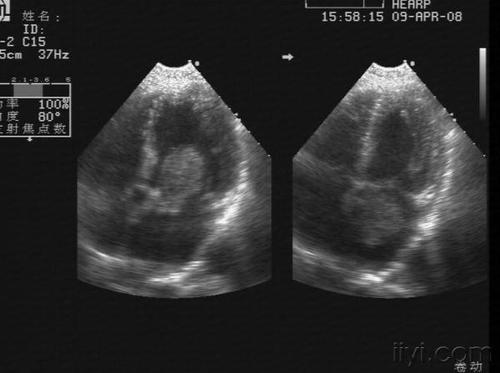

心房粘液瘤(超声心动图)

超声心动图见舒张期二尖瓣水平前后叶间一团块状回声 e:彩色多普勒瘤

超声心动图显示的巨大肿物,从心房突入心室